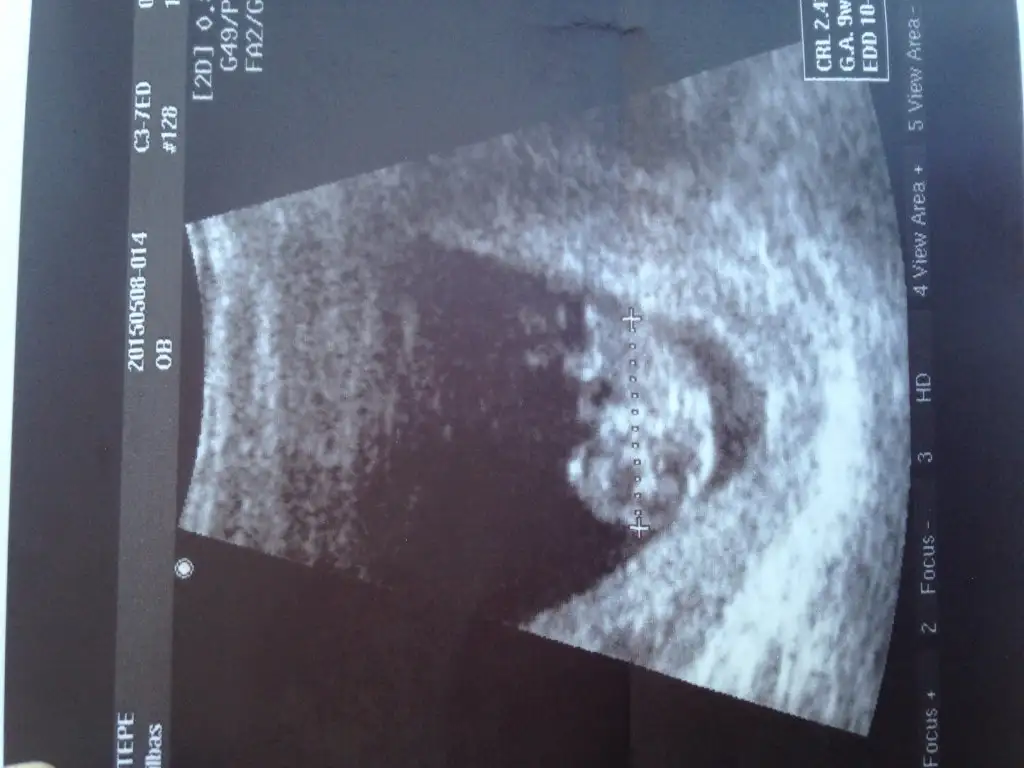

Kıza benziyor dedi ama 16. Haftada kesinleşir dediOnlarda da kıza benzettim ben. Erkekliğe dair belirgin bir şey görünmüyor. Doktor ne dedi?

Onlarda da kıza benzettim ben. Erkekliğe dair belirgin bir şey görünmüyor. Doktor ne dedi?Öncekilere de bakar mısın